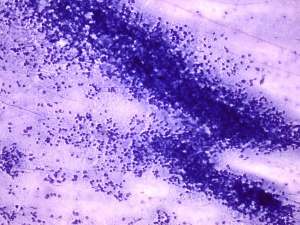

Cytology: suspicion of non Hodgkin lymphoma.

The cytological picture was identical with a small cell malignant tumor. Differential diagnostics included a metastatic small cell lung tumor and malignant lymphoma. The clinical presentation substantially decreased the likelihood of the former.